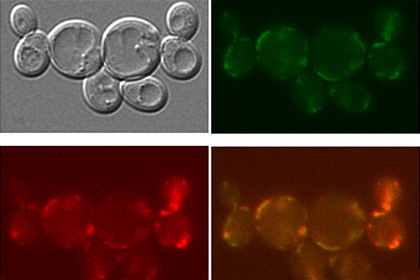

Исследователи из МГУ имени М.В. Ломоносова совместно со своими немецкими коллегами сумели доказать применимость кремниевых наночастиц для диагностики и лечения рака, впервые продемонстрировав их способность эффективно проникать в больные клетки и, выпустив заключенное в них лекарство, быстро разлагаться, не накапливаясь в организме. О деталях своей работы они рассказали в статье, опубликованной в последнем номере журнала Nanomedicine: Nanotechnology, Biology and Medicine.

Слева: Схематическое изображение процессов биодеградации кремниевых наночастиц: (I) локализация наночастиц на мембране клетки; (II), проникновение наночастиц в цитоплазму клетки, сопровождающееся частичной биодеградацией наночастиц; (III) полное растворение кремниевых наночастиц через 10-13 дней их инкубации в клетке. Справа: Спектры комбинационного рассеяния света (рамановские спектры) кремниевых наночастиц, снятые в течение различного времени их инкубации в клеткахMCF-7 (рак молочной железы): 9 ч, 48 ч и 13 дней инкубации изображены красным, синим и зеленым спектром, соответственно. Врезка: соответствующие изображения XZ-сечения клетокMCF-7, культивируемых с наночастицами, полученные с помощью рамановской спектроскопии. Источник: Любовь Осминкина -